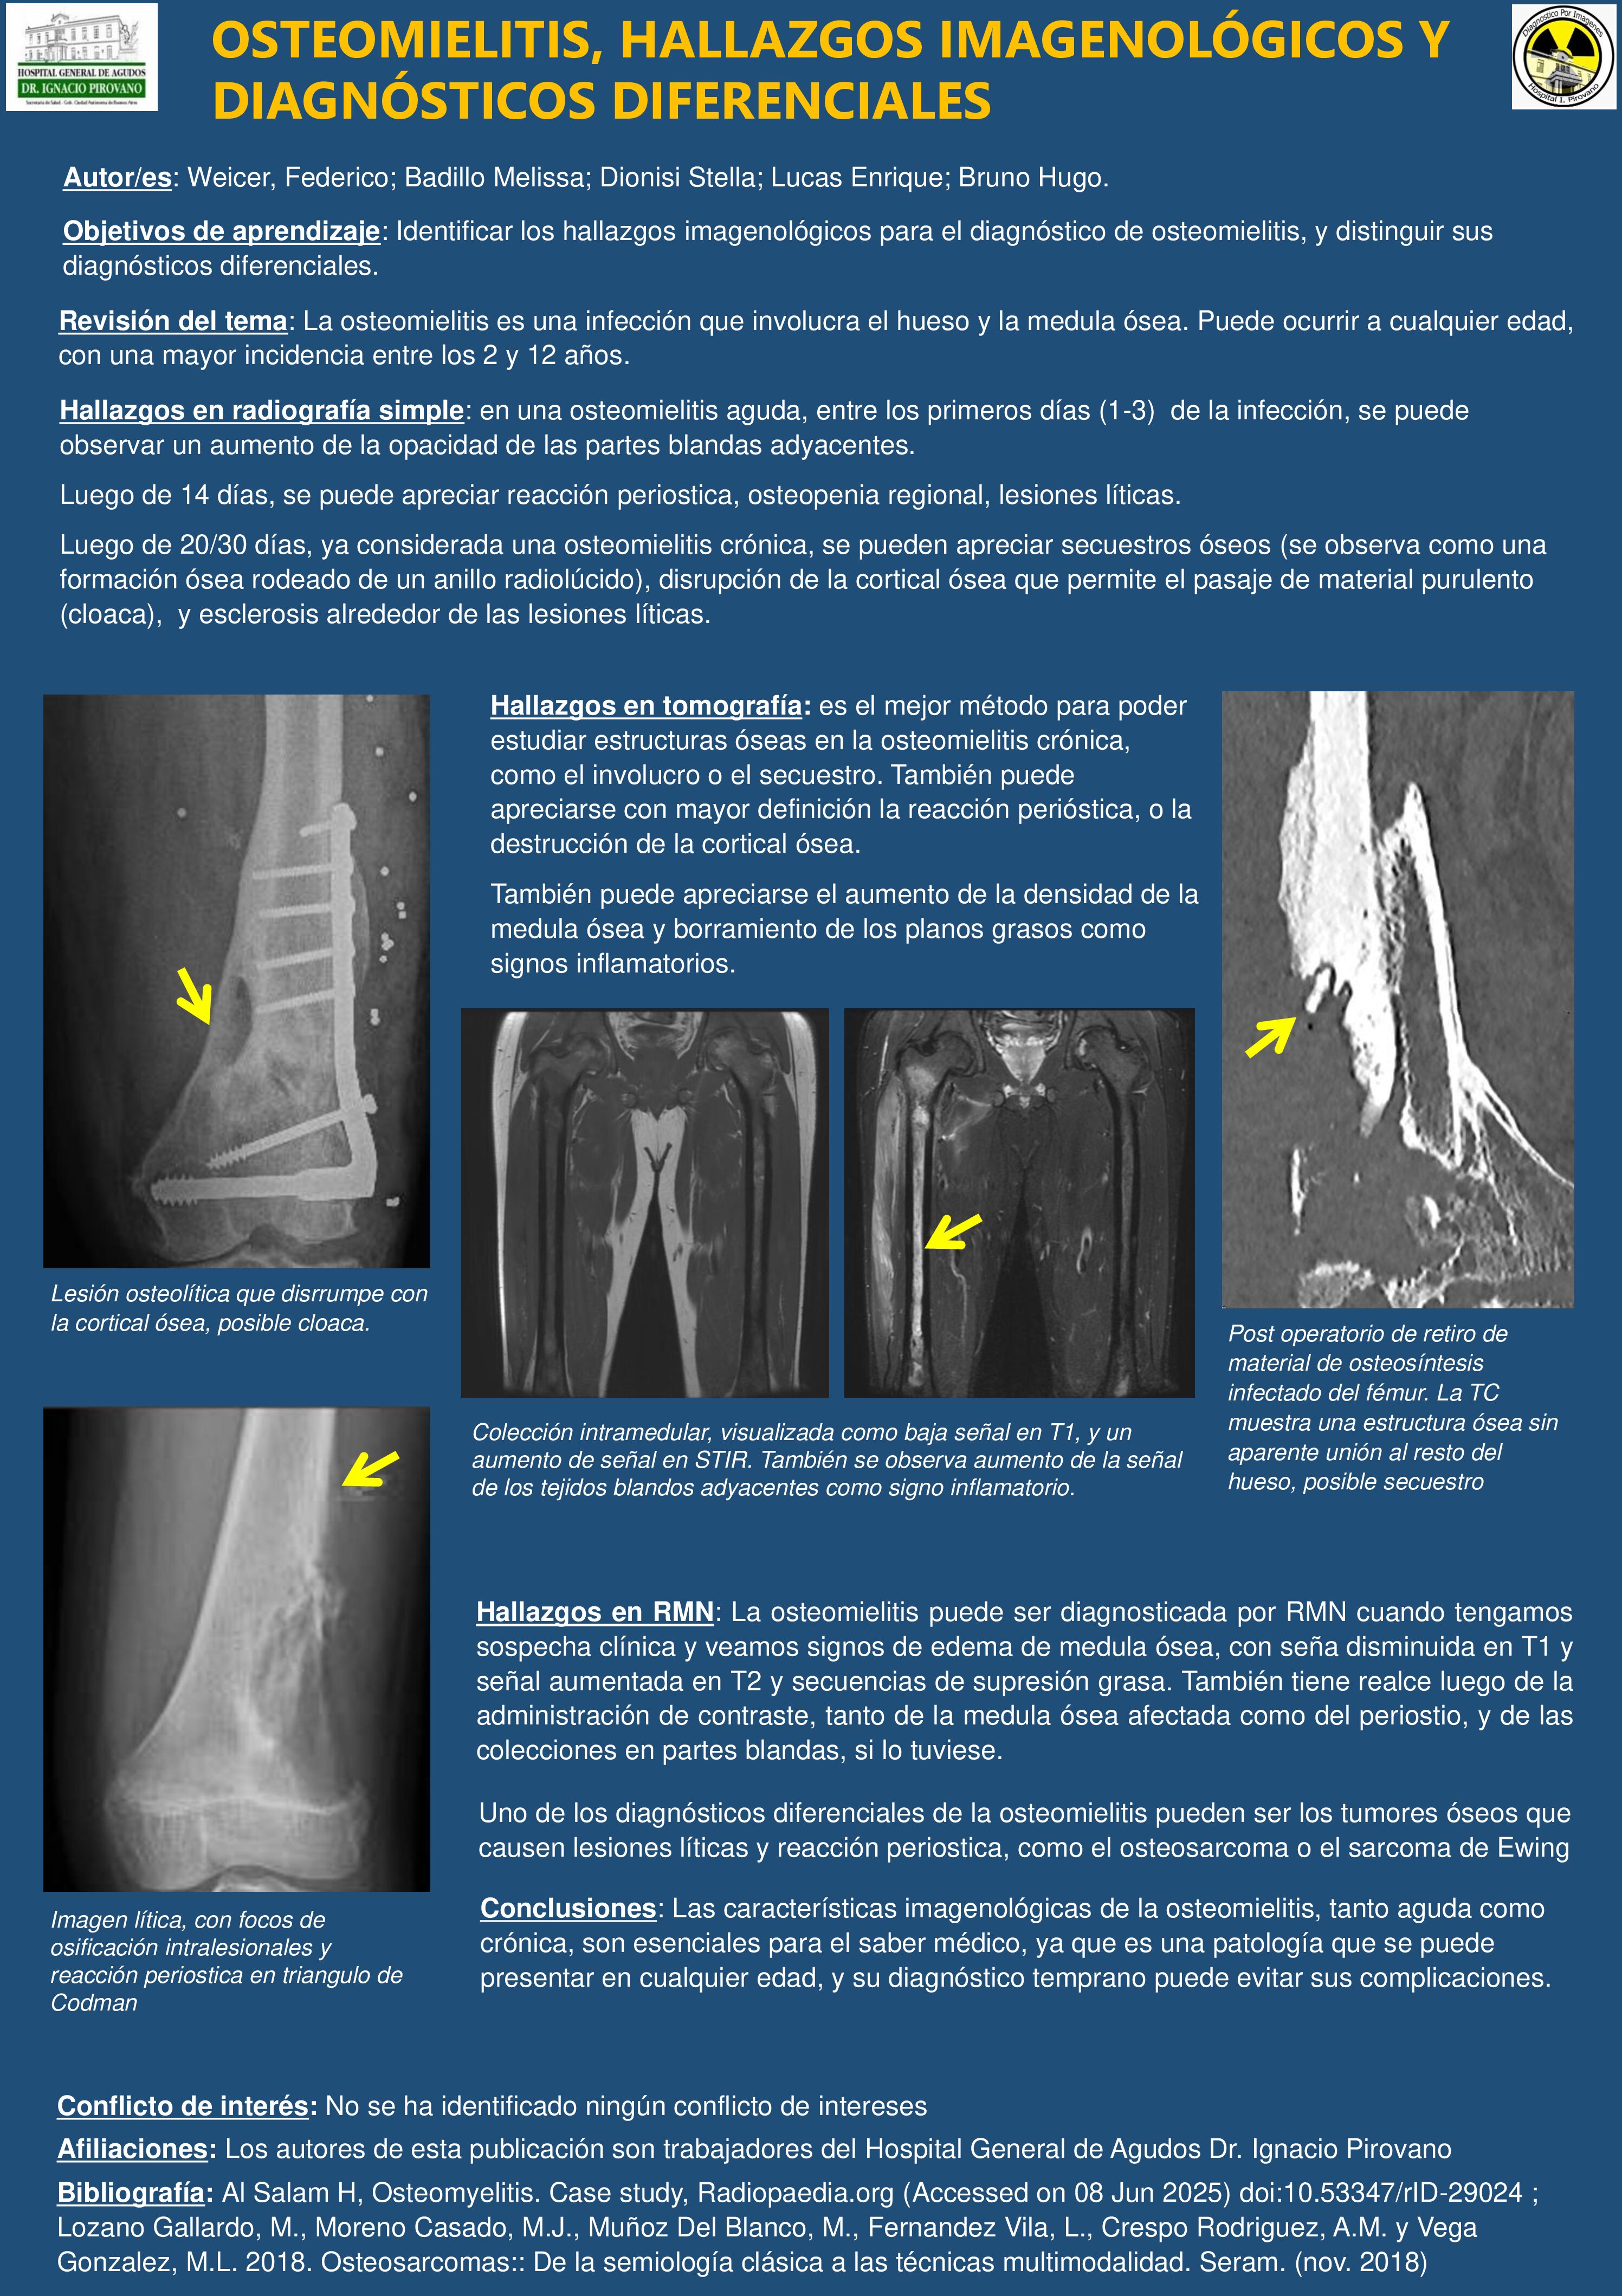

OSTEOMIELITIS, HALLAZGOS IMAGENOLÓGICOS Y DIAGNÓSTICOS DIFERENCIALES